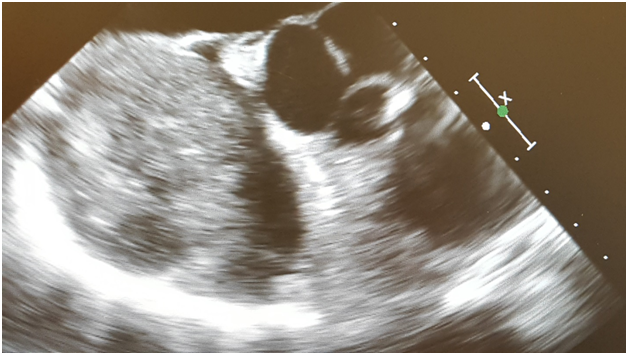

There was great concern regarding safe induction of anesthesia due to a near complete obstruction of superior vena cava (SVC). The patient was volume loaded with 500 milliliters of 5% albumin, 1.5 liters of crystalloid and 2 units of packed red blood cells. A right radial arterial line was placed preinduction. General anesthesia was delivered carefully using a induction regimen consisting of etomidate/ fentanyl/ midazolam and rocuronium for muscle relaxation. Surgeons were present in the operating room for induction. After induction of general anesthesia, a multiplane transesophageal echocardiography probe was inserted into the esophagus without difficulty. Transesophageal echocardiography revealed a very large mass in the severly dilated right atrium; the attachment point was not completely clear, but may have involved the atrial septum. The interatrial septum was intact with no evidence for an atrial septal defect. There was also mild to moderate tricuspid regurgitation. Left ventricle was normal in size with ejection fraction 55% (Figures 1 & 2). The patient remained hemodynamically stable throughout the case.

Figure 2: Transesophageal echocardiography midesophageal modified bicaval view demonstrates an extremely large right atrial mass with extension into the superior vena cava.